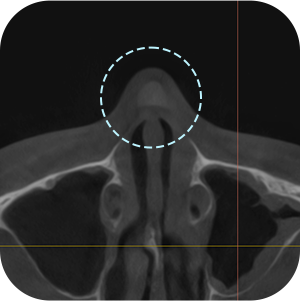

ตรจสอบผนังกั้นจมูก และโพรงจมูกภายใน

ตรจสอบตำแหน่งที่แน่นอน ของซิลิโคนเดิม

จำเป็นต้องถ่าย CT จมูกก่อนผ่าตัด ?

Aยิ่งเป็นกรณีผ่าตัดแก้ไข ก็ต้องยิ่งวิเคราะห์ละเอียดขึ้น!

การวิเคราะห์อย่างละเอียด จำเป็นอย่างมากต่อ การผ่าตัดแก้ไขจมูก

วิเคราะห์ได้อย่างละอียด

จากการถ่าย 3D-CT! - 03